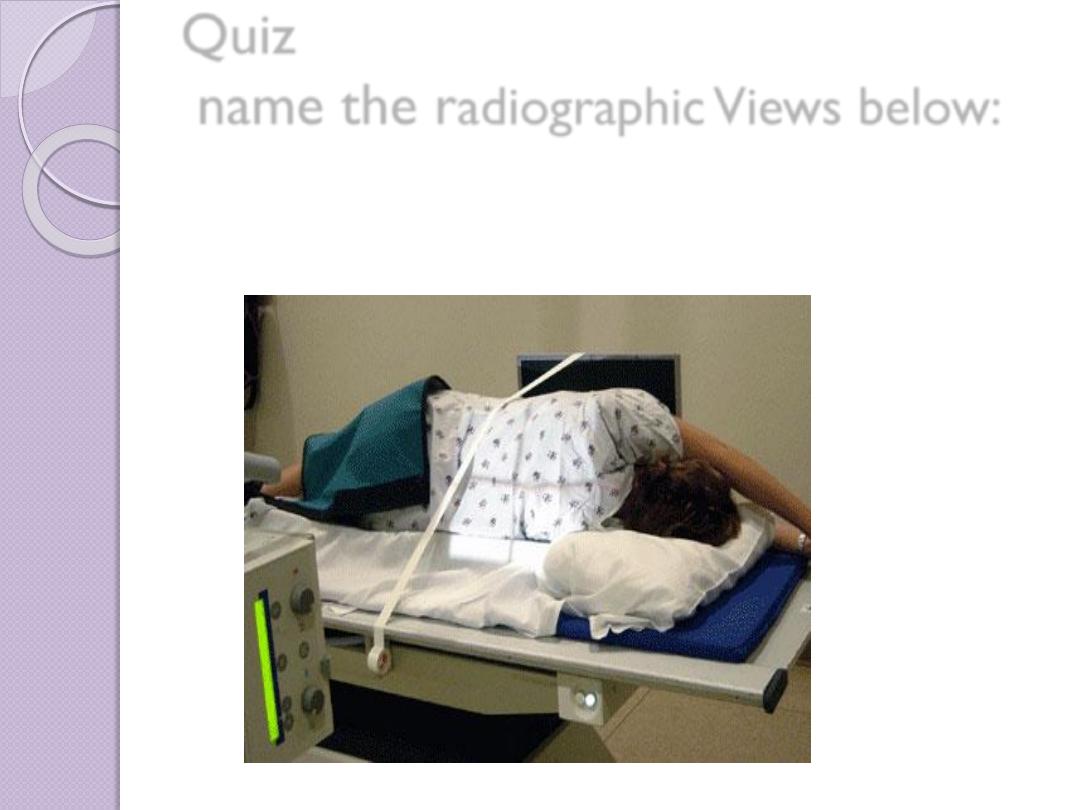

Radiographic Views

Chest and abdominal films are referred to as upright or

supine, depending on the position of the patient. In

addition, chest x-rays are usually described as

posteroanterior (PA) or anteroposterior (AP) or

lateral

These terms indicate the direction in which the x-ray

beam traversed the patient on its way to the detector.

PA means that the x-ray beam entered the posterior

aspect of the patient and exited anteriorly. AP means

that the beam direction through the patient was

anterior to posterior. A left lateral decubitus view is

one taken with the patient’s left side down.

Quiz

name the r

adiographic Views below: